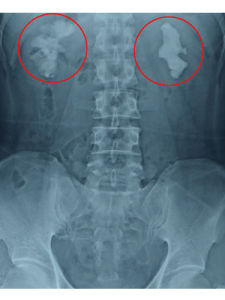

腎結石(calculus of kidney)指發生於腎盞、腎盂及腎盂與輸尿管連線部的結石。多數位於腎盂腎盞內,腎實質結石少見。平片顯示腎區有單個或多個圓形、卵圓形或鈍三角形緻密影,密度高而均勻。邊緣多光滑,但也有不光滑呈桑椹狀。腎是泌尿系形成結石的主要部位,其他任何部位的結石都可以原發於腎臟,輸尿管結石几乎均來自腎臟,而且腎結石比其他任何部位結石更易直接損傷腎臟,因此早期診斷和治療非常重要。 根據結石成分的不同,腎結石可分草酸鈣結石、磷酸鈣結石、尿酸(尿酸鹽)結石、磷酸銨鎂結石、胱氨酸結石及嘌呤結石六類。